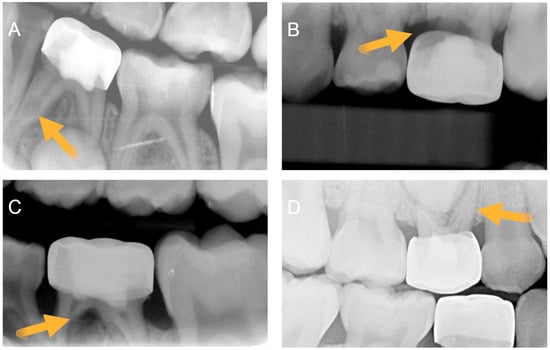

3.2. Calibration and Radiographic Assessment

- Radiographic pathosis—internal resorption without perforation, internal resorption with perforation, and/or furcation radiolucency.